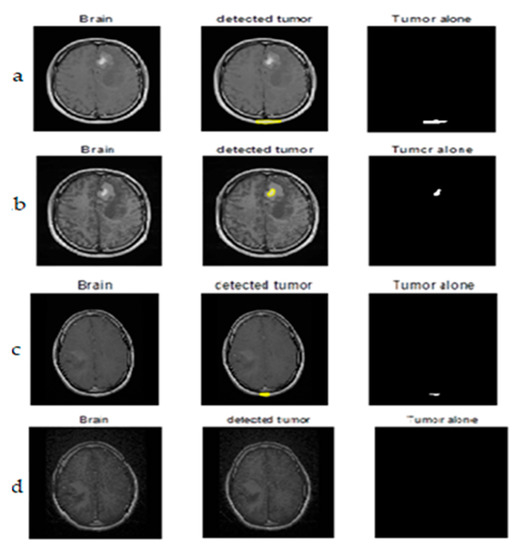

The upcoming figures are sectioned into three parts: Each part has an original neonatal brain image, and segmentation is achieved on that image. All the sections were subdivided into two parts—a and b. Part ‘a’ helps in visualizing tumor detection over the original image (which is not enhanced). On the other hand, part ‘b’ is of the enhanced image. Figure 10 represents the (a) original image, (b) preprocessed with BPDFHE enhanced image, (c) segmentation result using the median filter, (d) detection of the tumor, and (e) extraction of the tumor using thresholding.

Figure 10.

(a) Original image, (b) BPDFHE enhanced image, (c) segmentation result using median filter, (d) detection of tumor, and (e) extraction of tumor using thresholding.

The estimation of the proposed hybrid method for preprocessing and segmentation using a machine learning algorithm was shown on various MRI images to detect tumors. We placed the images for better visibility after simulations in ink space were used.

Justification of the results was carried out with the dice index (DI) and Jaccard index (JI). The ground truth (GT) image was considered to estimate the performance, which was prepared with the help of a radiologist.

The proposed ARKFCM technique considers spatial information of pixels for processing images which are affected by artifacts such as noise and intensity in-homogeneities. Hence, this procedure includes the effect of neighborhood pixels/voxels aimed at spatial information. Thus, it is capable of extracting boundaries in a proper way when compared to the existing, conventional FCM technique. It was witnessed that the implemented method was able to classify the effects of shielding and bright variations. Therefore, in brief, the main advantages of the proposed method were identified as robust to noise and shielding effects. The computable calculation was performed with Dice Index (DI) and Jaccard Index (JI) metrics [33], processing the difference between the segmented and GT images.

Segmentation results of the proposed method are shown in Figure 11 and Figure 12. The obtained numerical values are tabulated in Table 5 and Table 6 respectively, including the performance measures of dice similarity and Jaccard index. The proposed method provides efficient and robust results when compared to the FCM technique by a mean of a 98.86% dice index and 96.9% Jaccard index. This helps the physician to check whether the presence of any abnormalities is available in the MRIs corresponding to different parts of the brain. We conclude that the proposed remodified FCM technique ARKFCM method is more robust to noise and shading effects; the major advantage of using this technique is locating the tumor and affected regions.

Figure 11.

Tumor detection from original MRI brain images. (a) the first image in the is the original image, the second image is the segmentation image of the first image after preprocessing, and the third image represents detection of tumor alone. (b–d) rows consists of original brain images, segmented image with detected tumor, segmented tumor alone with proposed method respectively.